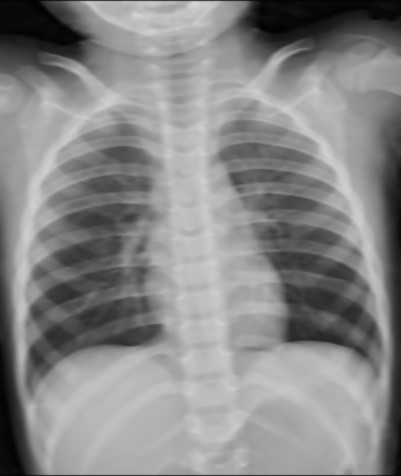

无滤线栅

|

通过以上病例可以看出同一个病人,分别在不使用滤线栅,使用实体滤线栅,和使用虚拟滤线栅之后图像,可以看到右边两幅图像的对比度较左边图像明显提高。而且国内临床数据显示肥胖患者明显优于正常体型和偏瘦体型。